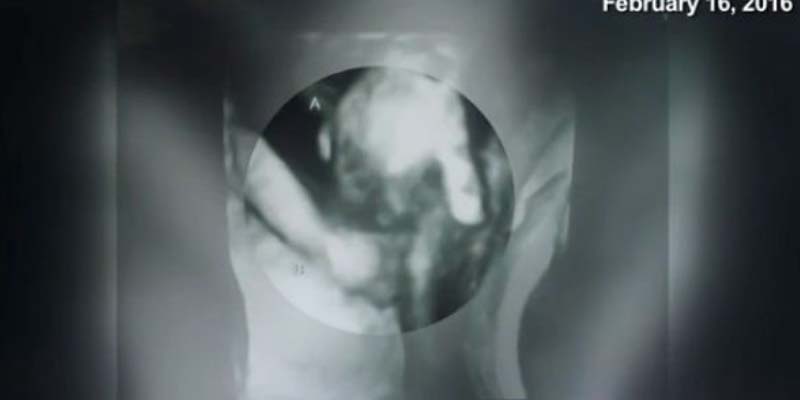

La imagen de los hermanos cogidos de la mano ha conmovido a los padres de los pequeños. Uno de ellos es probable que no llegue a nacer, pero la unión entre ellos ya es evidente. Los estudios científicos revelan que los bebés no nacidos sienten emociones y por eso, la madre cree que “Madilyn está siendo muy protectora con su hermano”.

“Sabemos que una parte de ellos permanecerá unida para siempre y eso es algo muy especial”, añade Ian McIntire. “No se ve demasiado bien, pero se puede apreciar una mano diminuta cogiendo la de su hermana melliza” aclara emocionado.

El emotivo momento de los mellizos cogiéndose la mano será una imagen que la familia McIntire atesore durante toda la vida.